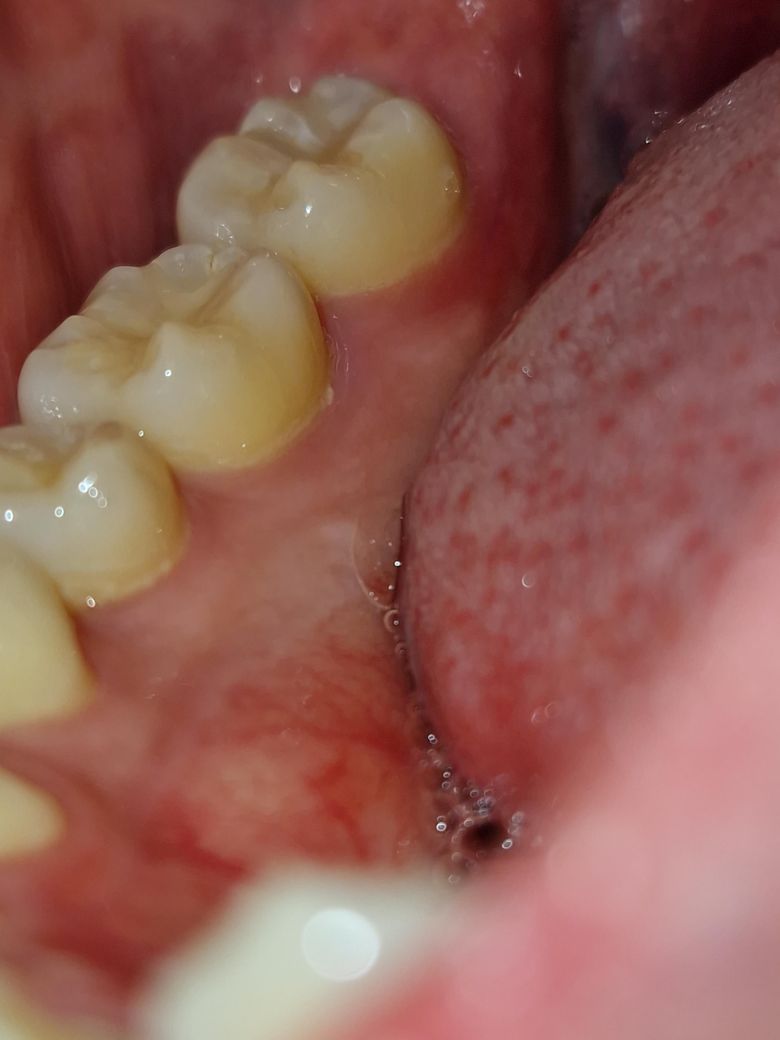

잇몸이 조금 빨갛고 말랑말랑 해진 것 같아요

어금니 쪽 잇몸 안쪽이 저렇게 빨개져있고 근처 잇몸이 약간 말랑거리는 느낌이에요. 통증이나 그런거 없고 잇몸 염증도 없었는데

어제까지 저렇게 빨갛지 않았는데 피곤해서 그런건지, 씹을 때나 양치 시에 생긴 상처같은 건지 자연 치유 될지 궁금합니다.

• 2번 째 사진